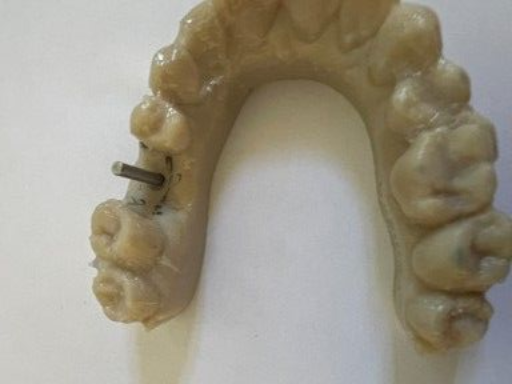

The surgical guide is ready

Implant axes materialized

Visualization of implant axes in reality from two angles, accurately confirming the software planning.